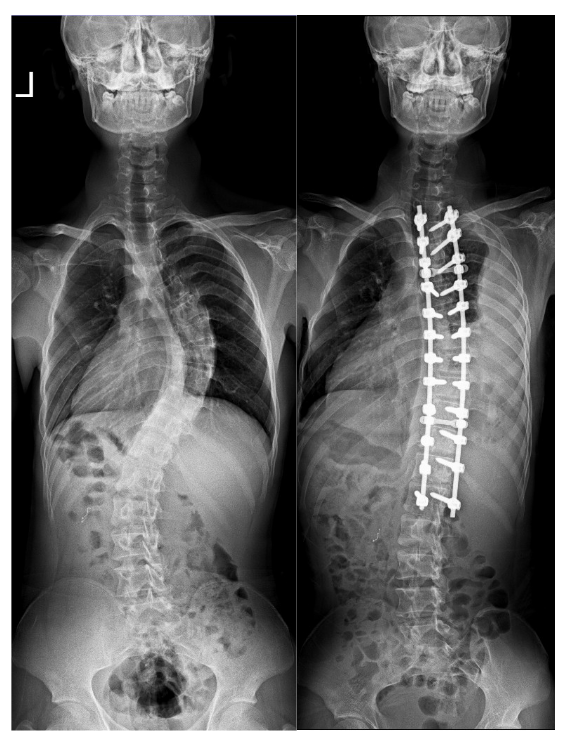

4月16日,华西天府医院骨科收治了石曲两兄弟。入院后询问病史得知,两兄弟多年前便出现胸背部高低不平,双肩不等高,身高增长不明显等问题。影像学显示:两兄弟脊柱呈“S”形侧弯畸形,双肩不等高,胸椎向右侧弯,腰椎向左侧弯,可见明显“剃刀背”畸形。其中一人并存肌性斜颈。

手术过程中,宋跃明教授、汪雷副教授运用了“经后路侧弯顶椎区多节段椎间盘切除、椎间隙松解+多节段SPO(Smith-Petersen Osteotomy)截骨技术,提高了僵硬型侧弯的柔韧性,再辅以华西脊柱侧弯撑开矫形去旋转工具,在保证脊髓神经安全的前提下,实现脊柱的三维畸形矫正,两位患者的侧弯矫正率分别达到了86%和78%,胸背部后凸畸形也得到了较好的矫正。

患儿1术前、术后影像资料

术后复查X光显示:脊柱侧凸和后凸畸形得到有效纠正,两患儿的身高分别增加了8-10cm,经宋跃明教授、汪雷副教授多次查房评估,两患儿恢复良好,并于5月8日顺利出院。